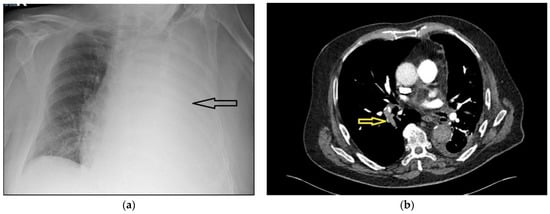

The pleural fluid analysis was consistent with an exudative process (fluid protein count 56 g/litre, plasma protein count 76 g/litre, glucose levels 6.2 millimole/litre, pH 7.35, serum lactate dehydrogenase (LDH) 456 units/litre, fluid LDH 300 units/litre). However, the patient remained persistently hypoxemic, with saturations of 92% on 40% oxygen, measured using a Venturi mask. Further discussion with the pleural team prompted a computed tomography pulmonary angiogram (CTPA) scan. The D-dimer of the patient was 4 milligrams/litre fibrinogen-equivalent units (mg/L FEU). The local reference range for D-dimer levels for patients who are more than 50 years old is calculated by the age of the patient divided by 100. Hence, for this patient, the normal range would be <0.75 mg/L FEU. Figure 1b shows a slice of the CTPA; this revealed a large right-sided pulmonary embolus and irregular pleural thickening on the left side, consistent with a pleural malignancy. Full-dose anticoagulation with tinzaparin was started and oxygenation improved over the next few days. Bilateral leg ultrasonography was performed and did not show any deep vein thrombosis. The chest drain was removed after cessation of drainage, and the patient was discharged with saturations of 93% on room air. Pleural fluid cytology yielded a predominantly lymphocytic effusion. The tumour cells were diffusely positive for thyroid transcription factor 1 (TTF1), and were consistent with primary lung adenocarcinoma.

Figure 1. (a) Chest radiograph showing a large left-sided pleural effusion (marked with arrow); (b) slice of computed tomogram scan showing a right-sided pulmonary embolism (marked with arrow), small left-sided pleural effusion and pleural thickening consistent with a pleural malignancy.